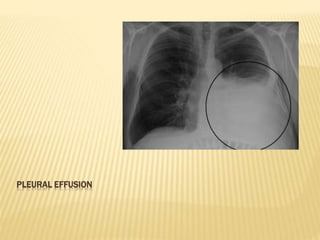

i) Erect chest X-ray P/A view:

The classical appearance of pleural fluid on

the erect PA chest film is of a curved shadow

at the lung base, blunting the costophrenic

angle and ascending towards the axilla.